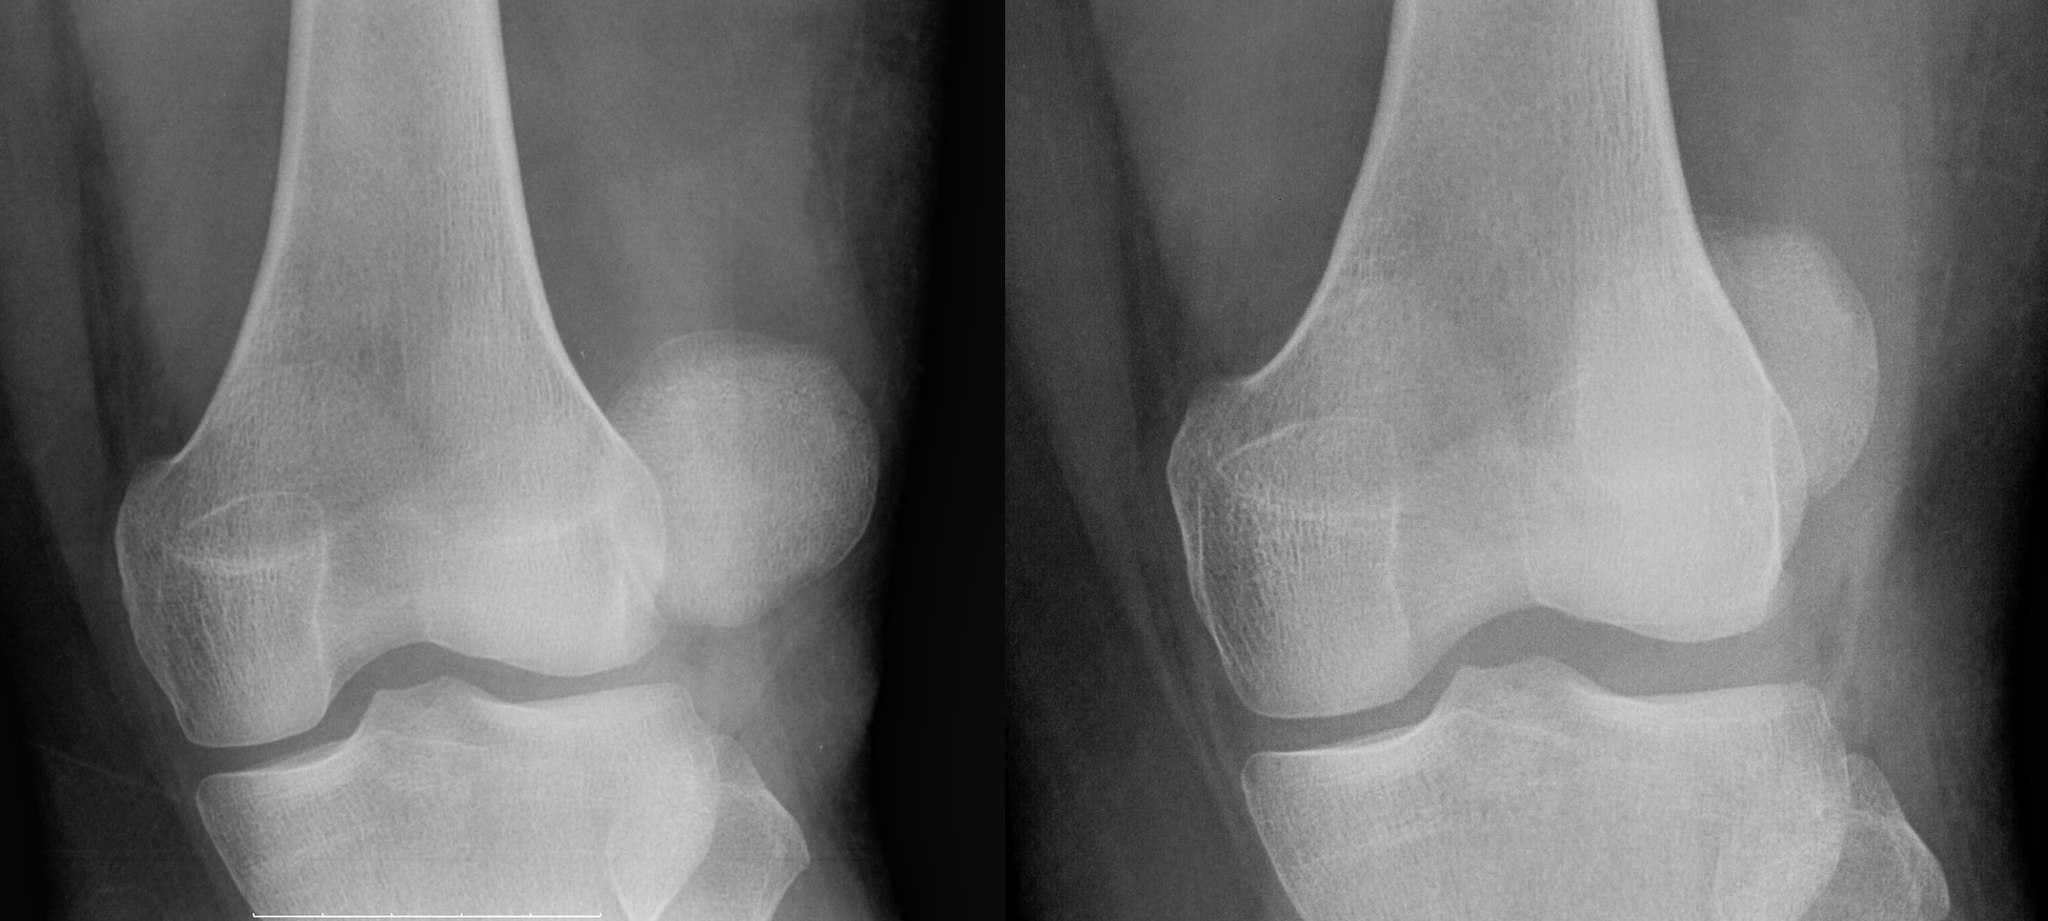

Commonly known as the “knee cap”, the patella can become dislocated. Drifting out of place, it tends to cause your animal to hold their leg in the flexing position. The slipped patella causing the knee to lock and hold. This can happen in both cats and dogs, often manifesting in smaller breeds. Severity and affect are variable. Grade 1-2 may include holding up the leg a few steps, or skipping to a more severe condition which may lead to being unable to extend the leg, bowing or a pigeon-toed posture.

There are surgical correction options available at TLC Pet Hospital. The surgery is designed to improve leg function and to resist degenerative joint disease with the stabilization of the patella in the trochlea. The surgery is a good option for older pets who have lost mobility. 95% of dogs undergoing the repair will produce significant improvement in knee function.